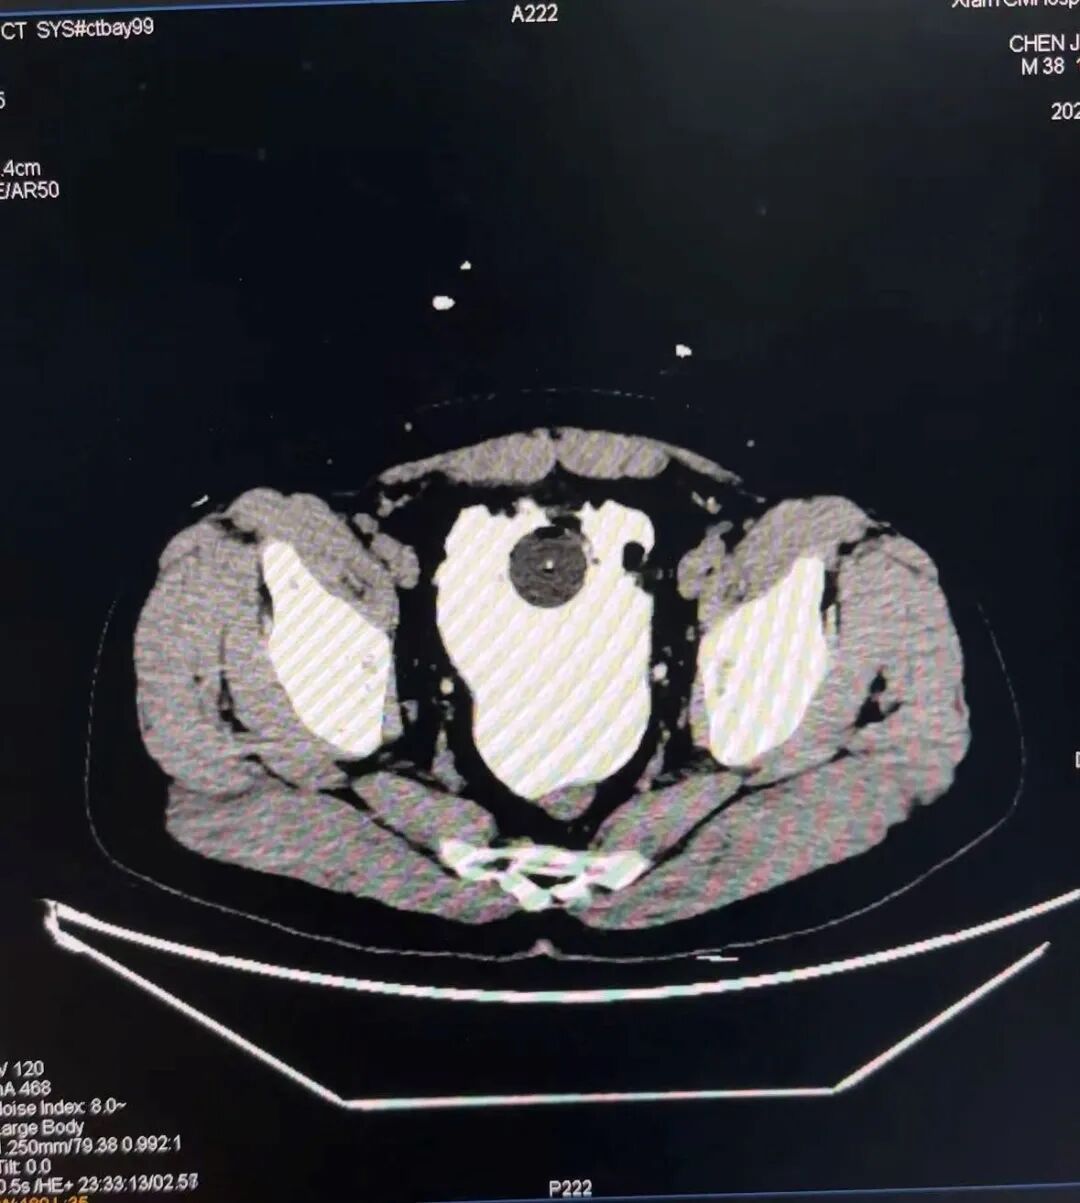

家人见状,立即将他送往西安市中医医院急诊科。此时的王先生已是面色苍白,冷汗直流。急诊科接诊医生向杰凭借丰富的临床经验,初步判断病情严重。腹部CT检查结果令人震惊——患者腹腔内存在大量不明积液。

“腹腔积液,结合患者的饮酒史和腹膜刺激症状,我们高度怀疑是空腔脏器破裂!”向杰当机立断,立即为王先生进行了腹腔穿刺,抽出的液体竟是淡血色液体,这完全不像是空腔脏器穿孔破裂出现的消化液性状。“难道是膀胱破了?”为了进一步明确诊断,急诊影像科团队又为患者实施了膀胱逆行造影,造影剂顺着破口溢出膀胱,清晰地显示了膀胱破裂的“犯罪证据”。

CT显示该患者膀胱完整性消失,造影剂外渗,提示膀胱破裂